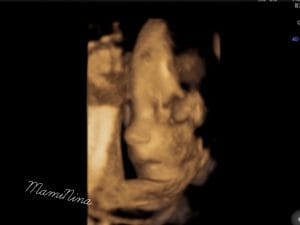

In resnično nam ni prav nič žal. Videli smo vse in to zelo dobro. Obrazek je seveda gospodična precej pokrivala, tako kot ga je tudi njena sestrica. In ne le to, prav tako kot sestrica, je tudi tale gospodična obrnjena v desno, pred obrazkom se nahaja tudi ena nogica in seveda kraljuje na svoji mali ritki.

Seveda pa prilagam tudi 4D ultrazvok male zaspanke, ki je načeloma ves čas zelo aktivna, tokrat pa je na pregledu bolj ali manj počivala.